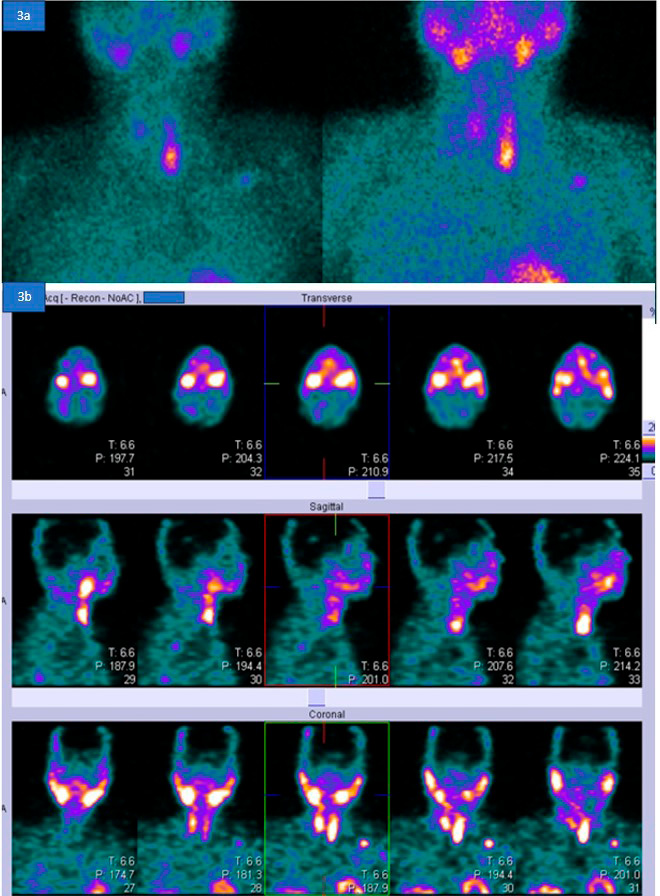

La ecografía del cuello mostró una lesión nodular bien definida iso- a hipoecoica adyacente al polo inferior del lóbulo tiroideo izquierdo, probablemente un adenoma paratiroideo benigno. La gammagrafía paratiroidea y la SPECT- TC mostraron captación anormal del trazador en un nódulo hipodenso debajo del lóbulo tiroideo izquierdo, de 1,8 × 1,4 × 2,5 cm, consistente con un adenoma paratiroideo (Figura 4).

Figura 4.

Figura 4a. La gammagrafía paratiroidea con 12 mCi de Tc-99m tetrofosmina, incluyendo imágenes tempranas y tardías, revela una captación focal aumentada del trazador inferior al lóbulo tiroideo izquierdo. Se observa una captación difusa de bajo grado en el resto de la glándula tiroides, con un aclaramiento muy lento del trazador y una retención focal del mismo inferior al lóbulo tiroideo izquierdo.

Figura 4b. SPECT-TC que muestra una captación anormal del trazador en un nódulo hipodenso debajo del lóbulo tiroideo izquierdo, midiendo 1,8 × 1,4 × 2,5 cm, consistente con un adenoma paratiroideo.